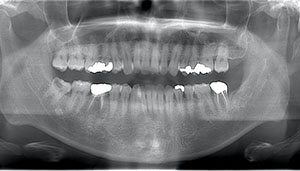

左下の歯茎が腫れている親知らずの症例

- 抜歯前写真(レントゲン、CT等)

左下の親知らず周囲歯肉が腫れていました。

また、手前の歯との間で虫歯もできていました。

3分割して抜歯しました。

| 年齢 | 20代・女性 |

|---|---|

| 主訴 | 左下の歯茎が腫れている |

| 適応するプラン | スタンダード親知らず抜歯プラン |

| 親知らずの生え方 | 歯茎から少し頭が出ている |

| 抜歯時間 | 15分 |

| 費用 | 約7,000円 |

| 抜歯内容 | 下顎の親知らずの抜歯希望の患者様です。 智歯周囲炎となっており、初診時では麻酔が効きづらい旨をお話しし、初診時は抗生物質をお出ししました。1週間後、ある程度歯肉の炎症がとれたことを確認して抜歯を行いました。 麻酔を行い、遠心(親知らずの奥側)歯肉と、手前の歯の頬側の歯肉を切開しました。 歯茎を開いて、手前の歯と引っかかっている部分をカットしました。 その後、骨からでている歯冠部(頭の部分)をカットしました。 その後へーベルで歯根(骨に埋まっている部分)を脱臼し、抜歯を終えました。 切開した歯茎を3針縫って、治療終了となりました。 歯茎を切ったため、3日ほど腫れぼったい感じがあったようですが、痛みはほとんどなく、治癒に向かいました。 |